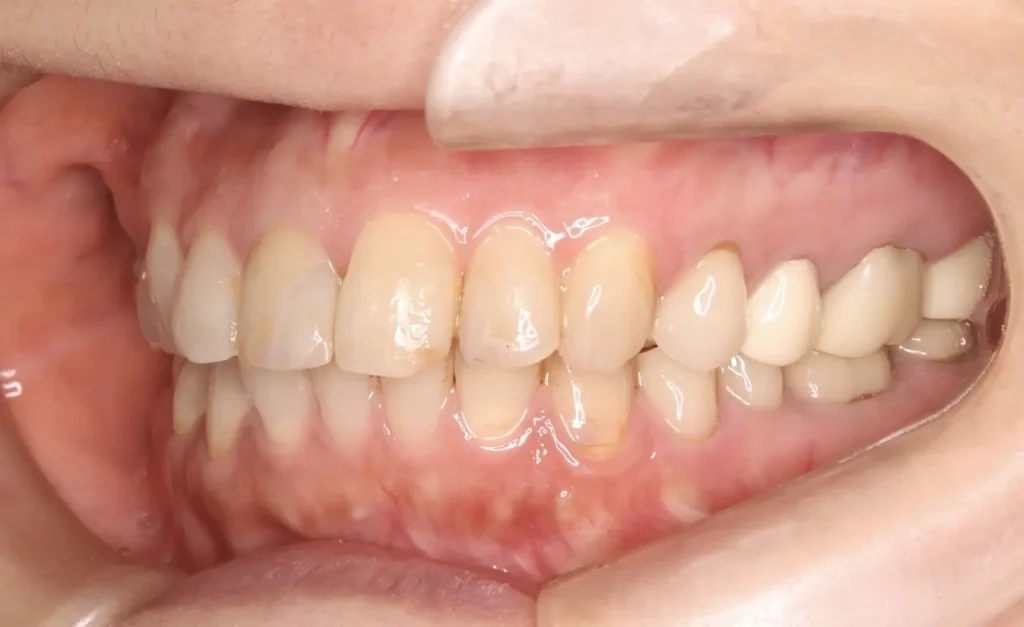

術後1年口腔内写真

ウミの出口もなくなり外科的処置の跡はほとんどなく、被せ物も天然歯と見分けつきません

外科的処置の跡はほとんどなく、ブリッジも自然な感じで歯がないようには見えません